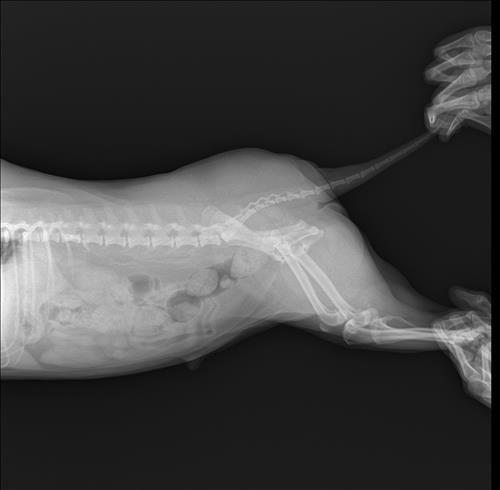

2016년생 10세 8kg 비숑입니다

오른쪽 뒷다리를 서있을째 떨다가 이젠 깽깽이발을 하길래 근처 동물병원을 갔더니 십자인대가 손상됐다고 했어요 파열이 아니라 체중감량하고 약물 처방 해줬다는데 진통제라 치료의 개념은 아니라고 생각하는데 근본적인 치료는 수술이 맞을까요..?